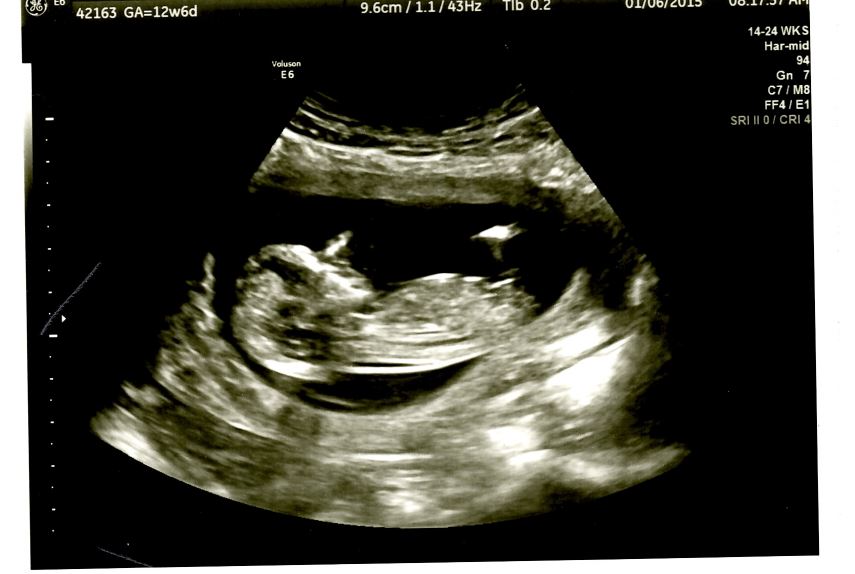

This was taken at 12 weeks 6 days. I would love some opinions on whether this is boy or girl based on nub, i've had mixed responses from other gender prediction sites and my curiosity is now killing me!!!! Attachment 23216

Anyone??? Nub theory or skull predictions appreciated!!

I don't think that line is the nub. It seems to far up? So I'm not sure what baby is, sorry!

I can definitely see why you got the mixed responses. I cant tell if its noise interference I see or you have the makings of a boy nub.

I appreciate your honest answers. I didn't think it would be this tricky ! If that isn't infact the "nub" what would be?? Something further down? I see a couple other things sticking out below it